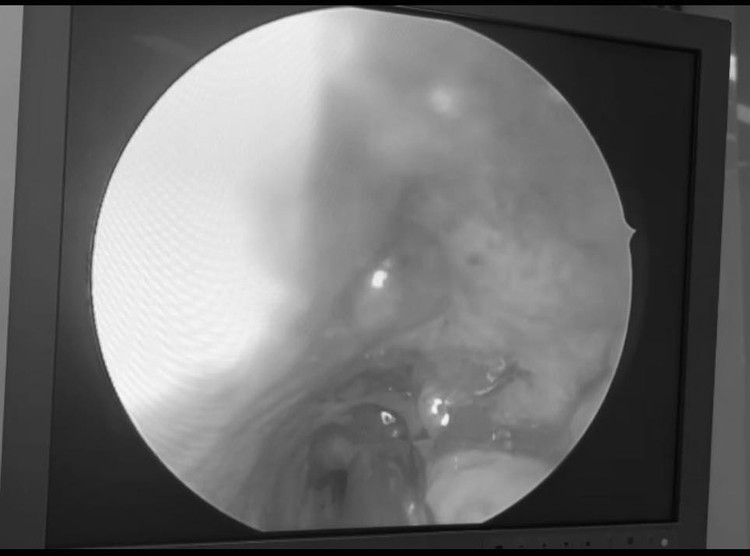

Khi vào viện bệnh nhân trong tình trạng mệt mỏi, da xanh, niêm mạc nhợt, mũi hai bên đang có Merocel cầm máu, sau khi rút Merocel kiểm tra thấy điểm chảy máu ở cuốn dưới động mạch bướm khẩu cái. Ngay lập tức Bệnh nhân được giải thích tình trạng bệnh và đưa vào phòng phẫu thuật để thực hiện Phẫu thuật nội soi cầm máu mũi cấp cứu.

| Phải mổ cấp cứu và truyền máu khẩn cấp vì chảy máu mũi |